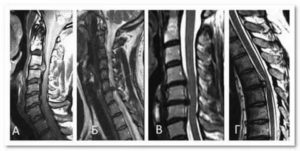

- МРТ. Наиболее информативный способ диагностики. Позволяет получить полную картину состояния всех видов тканей позвоночника. Процедура безболезненна и может проводиться многократно в течение короткого промежутка времени.

- Компьютерная томография. Дает полное представление о размерах межпозвоночных дисков и наличии выпячивания в их структуре.